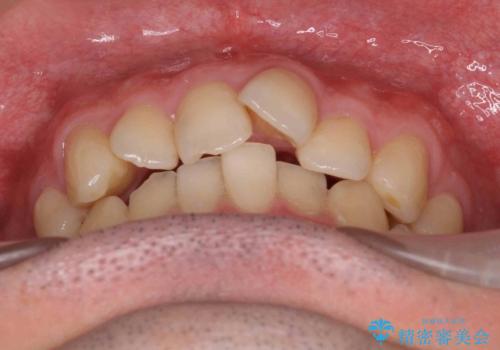

受け口、すきっ歯を インビザラインで モニター治療

- 前歯のすき間と受け口を気にして来院。

下の前歯を後方に移動するため、ゴムを上下のマウスピースにかけてもらいました。